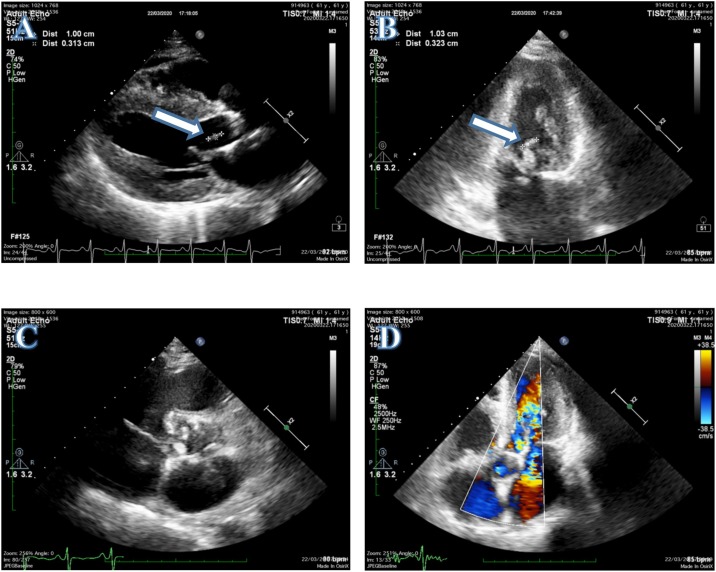

Transthoracic echocardiogram: (A) PLAX view showing a vegetation in the anterior mitral leaflet (white arrow). (B) Two chamber view confirming a vegetation in the anterior mitral leaflet (white arrow). (C) Calcified aortic cusp of rheumatic heart disease. (D) Five chamber view with Doppler signal showing aorta regurgitation.

Arterial blood gas analysis showed no abnormality, with pH 7.43, PaCO2 38.5 mmHg, PaO2 89.4 mmHg, HCO3 − 21.7 mmol/l, and SaO2 94.6%. A transthoracic echocardiogram (TTE) revealed a flail mitral leaflet with a vegetation measuring 10 mm × 3 mm in size, producing severe mitral regurgitation, dilatation of the left heart and right atrium, and moderate aorta regurgitation. These findings suggested that the patient was suffering from RHD and IE (Figure 2 ) nasopharyngeal swab test reverse-transcription polymerase chain reaction (RT-PCR) assay was performed to confirm COVID-19. While awaiting the results, the patient was quarantined in the isolation room.

The TTE results were considered to indicate RHD complicated with IE. IE was established based on the modified Duke criteria, along with three minor criteria (Osler node lesions, splinter hemorrhages, and fever) (Li et al., 2000). The negative culture results in our center, however, probably resulted from the previous administration of antibiotics in the referral hospital. We could not proceed to investigate the microorganism causing IE, as serological testing and PCR using blood or valve biopsies could not be performed during this pandemic era in our center. Moreover, based on the TTE, we found severe mitral regurgitations with jet length ≥2 cm, velocity ≥3 m/s, and moderate aorta regurgitation seen in two views. These TTE findings confirmed that the patient was suffering from RHD (Reméanyi et al., 2012).